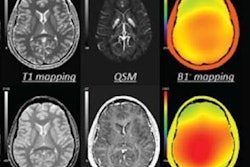

The purchase adds a team of engineers and physicists to SpinTech's roster, as well as 10 patents and a network of more than 50 collaborators around the world. The two firms have worked together previously, in particular, to develop a standardized MRI software program for artificial intelligence-assisted MRI.